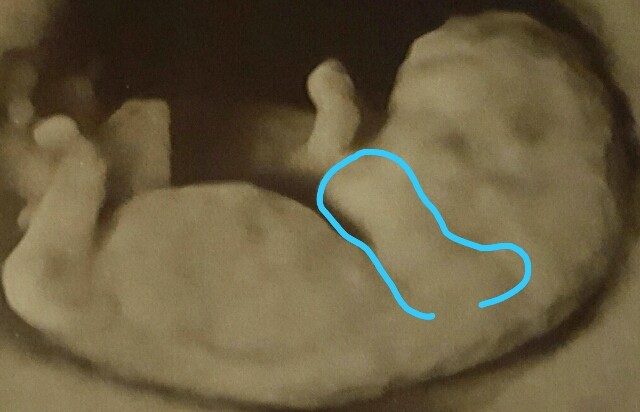

Nawet śmiałabym twierdzić że twoja śliczna dzidzia ssie sobie paluszki

Jest rączka. Widać ramieJa widzę raczke od naszej strony, zachodzi pod brodę :-)

Ja też widzę obie rączki , ta od naszej strony tak jakby na nos pokazywała